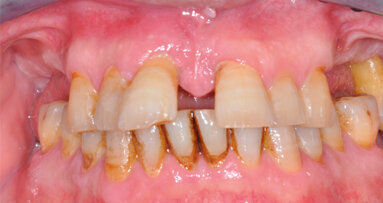

La paziente, donna di 26 anni, presentava agenesia bilaterale degli incisivi laterali superiori. Affermava di voler risolvere la problematica il più velocemente possibile per motivi di natura sia psicologica sia economica, esprimendo il desiderio di ottenere una riabilitazione funzionale ed estetica tramite un intervento finalizzato alla realizzazione di una protesi fissa. È stato quindi prospettato un approccio terapeutico multidisciplinare basato su trattamento ortodontico per migliorare l’allineamento e ottimizzare lo spazio per il posizionamento implantare. Dopo accettazione e firma del consenso, si è proceduto al trattamento ortodontico fisso. In una prima fase, due elementi provvisori a pura funzione estetica sono stati apposti all’apparecchio ortodontico (Fig. 1a). Ottenuto il risultato ortodontico a distanza di 12 mesi (Fig. 1b), si è potuto procedere con l’inserimento di impianti B1ONE (IDI Evolution) a diametro ridotto.

Fig. 1_Presentazione del caso. Il paziente presenta agenesia bilaterale degli incisivi secondari superiori; a) trattamento conservativo con provvisori in resina solidarizzati all’apparecchio ortodontico e a sola funzione estetica; b) trattamento ortodontico per l’ottimizzazione del piano occlusale e dello spazio mesio-distale.